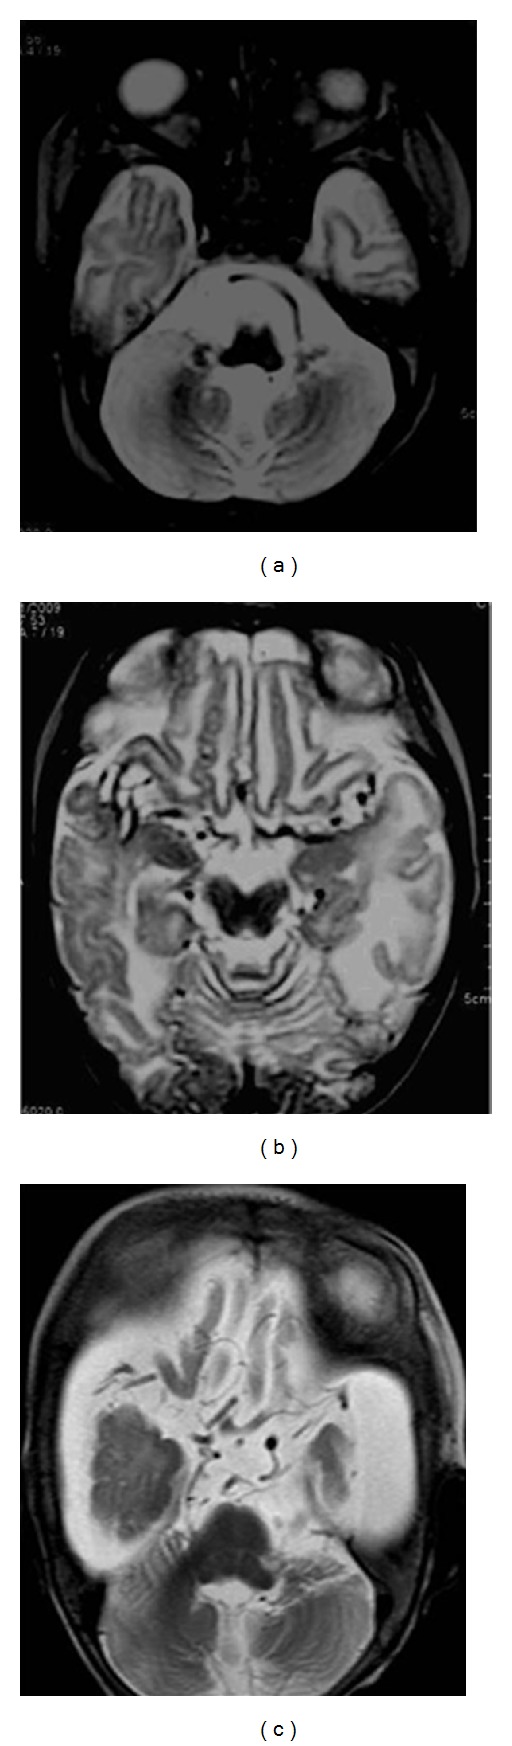

Figure 3.

Atrophy of the cerebellum with prominence of cerebellar folia. Asymmetric cortical and subcortical hyperintensities on the axial T2WI predominantly in bilateral temporoparietal regions with involvement of the insular cortex.

MRI showed diffuse bilateral white matter hyperintensities on T2-weighted sequences. Symmetrical cerebral and cerebellar atrophy was seen, the latter being more prominent (Figure 3). Extradural and subdural hemorrhages of various stages were identified, one showing fluid-fluid levels in high parietal region (Figure 4). On MR angiography, tortuosity of internal carotid arteries, proximal middle cerebral arteries with distal narrowing were seen (Figure 5).

T2(TR: 5000, TE: 102) and fluid-attenuated inversion recovery (TR: 9000, TE: 2500) weighted axial image of brain on Siemens 3 Tesla TIM Trio machine showing bilateral subdural collections of differential intensities suggesting different ages of these hemorrhages.